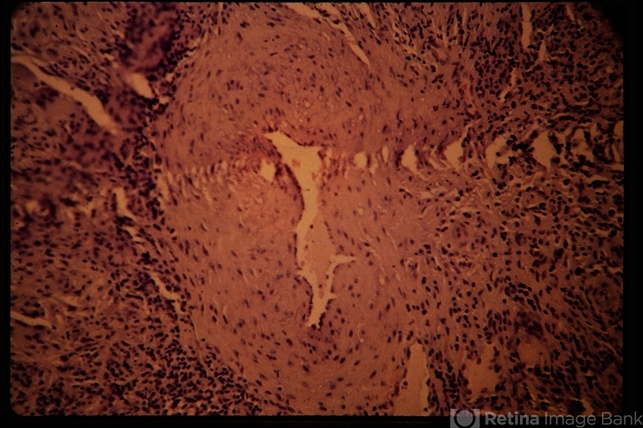

- Temporal Arteritis

- giant cell arteritis

- Temporal artery biopsy specimen showing multi-nucleated giant cells.